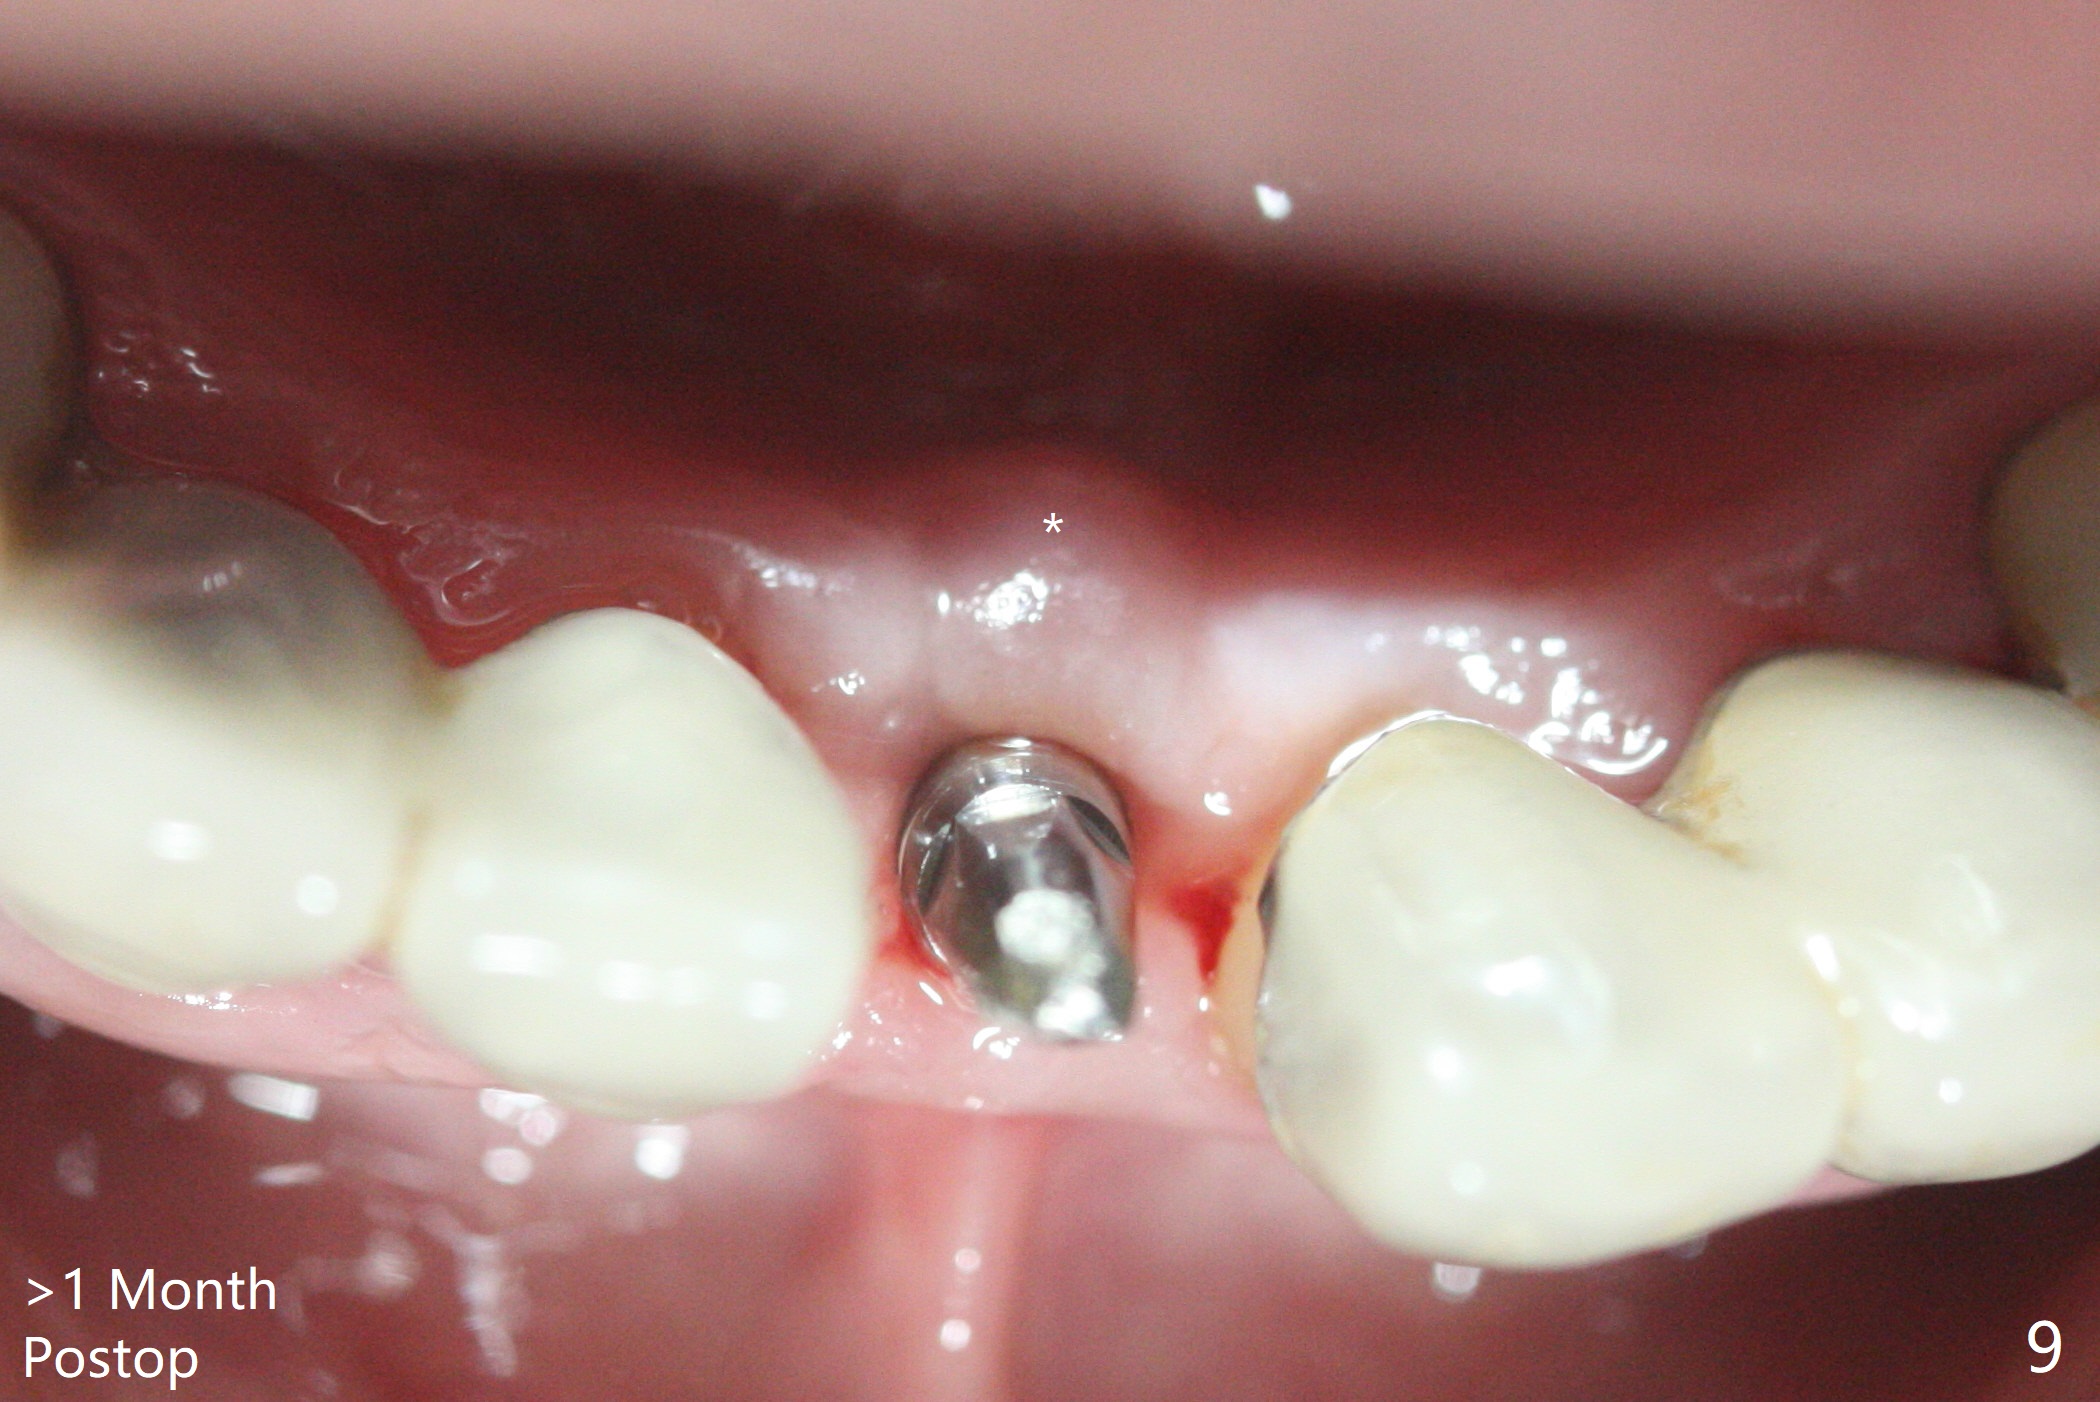

种植前与66岁女病人再次讨论下前牙正中种植可能产生不对称问题,她好像不在乎。术前检查显示下前牙正中间隙偏左(图一),处理似乎容易,但是牙槽嵴相当狭窄(图一 *,二 箭头)。牙槽嵴切除后(大约3 毫米宽(颊舌侧)),初期钻洞似乎偏移右边(图三),矫正后(图四),植入2乘10(4)毫米连体植体(图五,比预计小,因为骨质薄),放置骨粉(图五,六 *)和膜,缝合,制作即刻修复物(图七 T),病人满意,牙槽骨饱满了。术后一个多月临时牙冠取出修正,伤口愈合,由于植骨颊侧没有凹陷(图八),而舌侧隆起(图九:*,与图二术前对比)。其实病人不小心吃牛肉时损伤植体,疼痛几天。尽管最近吃饭时植牙又受伤,但是没有松动,也没有骨质吸收,就是局部结石多(图十,术后四个月)。正式牙冠术后4.5个月粘固(图十一)。